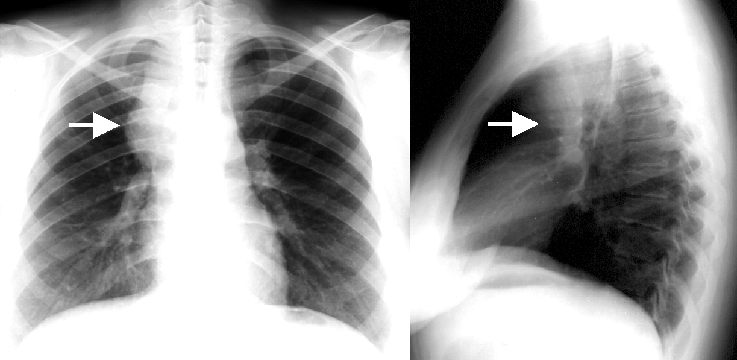

5a,b: Lung abscess. Chest radiograph, bidirectional (PA+lateral - right side near the film).

61 year old woman. Laparoscopic esophagus diverticulum resection 2 months ago. 7 cm air-fluid level with air space above: „basket sign” above the right diaphragm laterally measuring 2,5 cm in lateral diameter and 7 cm mediodorsally.